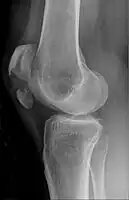

| A fracture of the patella seen on a lateral view | |